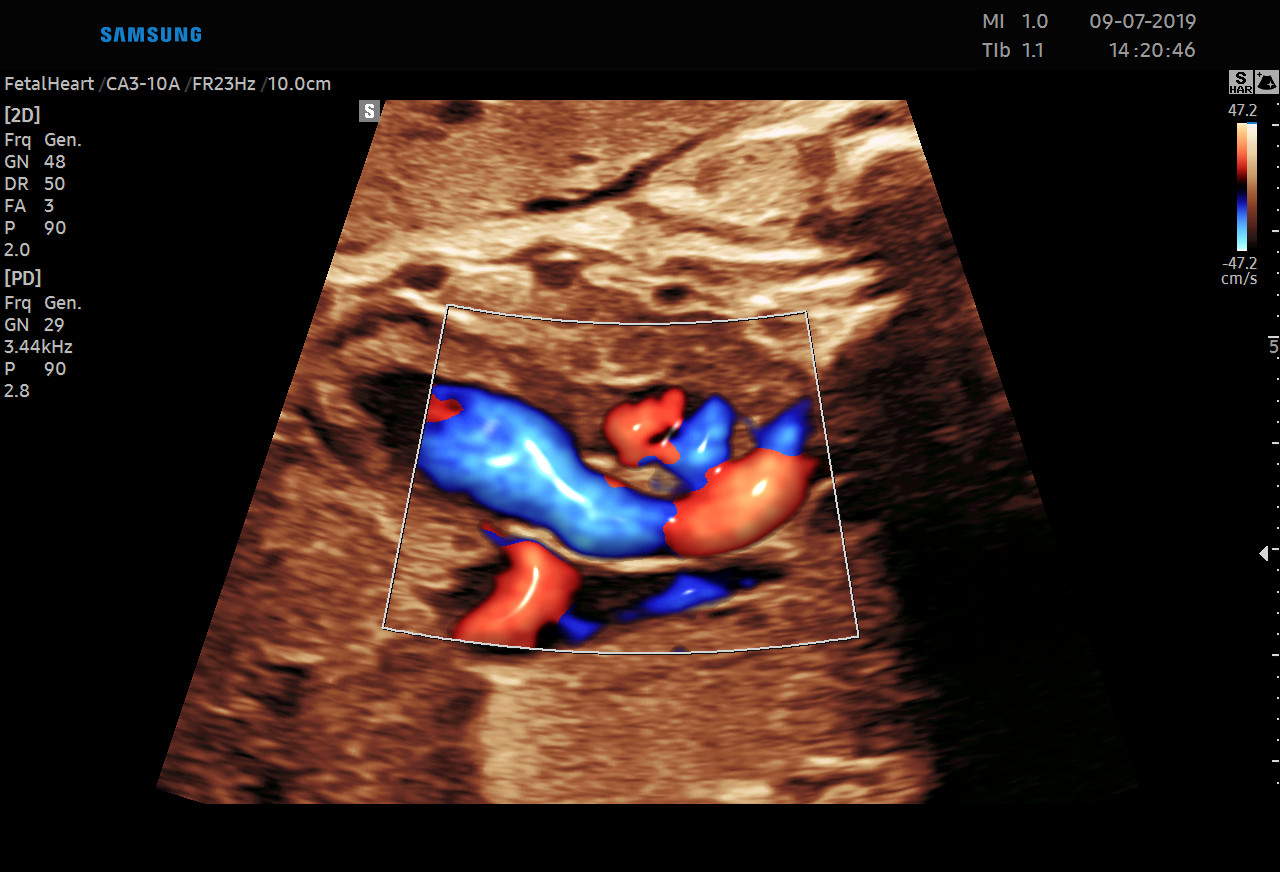

Diagnostykę obrazową przeprowadzamy z wykorzystaniem sprzętu Samsung HERA W9. To najnowszy aparat klasy premium – z kompletem głowic USG wysokiej rozdzielczości w tym głowicą USG 3D/4D. Doskonała jakość obrazu przekłada się na wiarygodność wyników.

• USG ginekologicznym i w czasie ciąży wtym 3D/4D.

Dostęp do nowoczesnej aparatury pozwala na obrazowanie przepływów w naczyniach krwionośnych. Dlatego wykonujemy również badania USG Doppler:

Ponadto jesteśmy w stanie zmierzyć przepływy w naczyniach u kobiet ciężarnych oraz płodu.